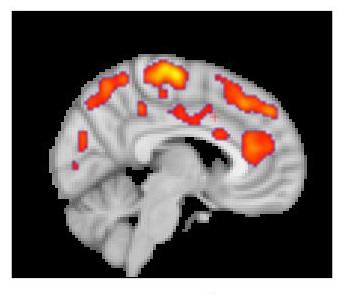

The results from both centers found that glial activation in several regions of the brains of fibromyalgia patients was significantly greater than it was in control participants. Compared to the MGH team's chronic back pain study, TSPO elevations were more widespread throughout the brain, which Loggia indicates corresponds to the more complex symptom patterns of fibromyalgia. TSPO levels in a structure called the cingulate gyrus - an area associated with emotional processing where neuroinflammation has been reported in patients with chronic fatigue syndrome - corresponded with patients reported levels of fatigue. The Karolinska team's studies with the astrocyte-binding tracer found little difference between patients and controls, suggesting that microglia were primarily responsible for the increased neuro-inflammation in fibromyalgia patients.